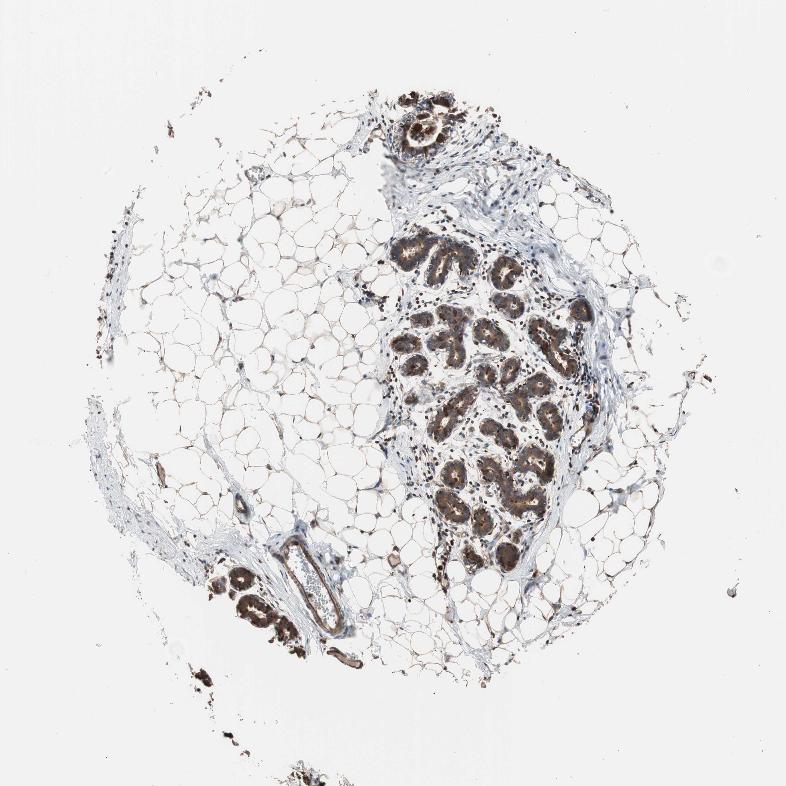

BREAST - Antibody stainingi

Antibody staining in the annotated cell types in the current human tissue is reported as not detected, low, medium, or high, based on conventional immunohistochemistry profiling in selected tissues. This score is based on the combination of the staining intensity and fraction of stained cells.

Each image is clickable and will lead to virtual microscopy that enables deeper exploration of all samples and also displays staining intensity scores, fraction scores and subcellular localization as well as patient and tissue information for each sample.

Antibody HPA006543

Adipocytes Low

Glandular cells High

Myoepithelial cells Medium